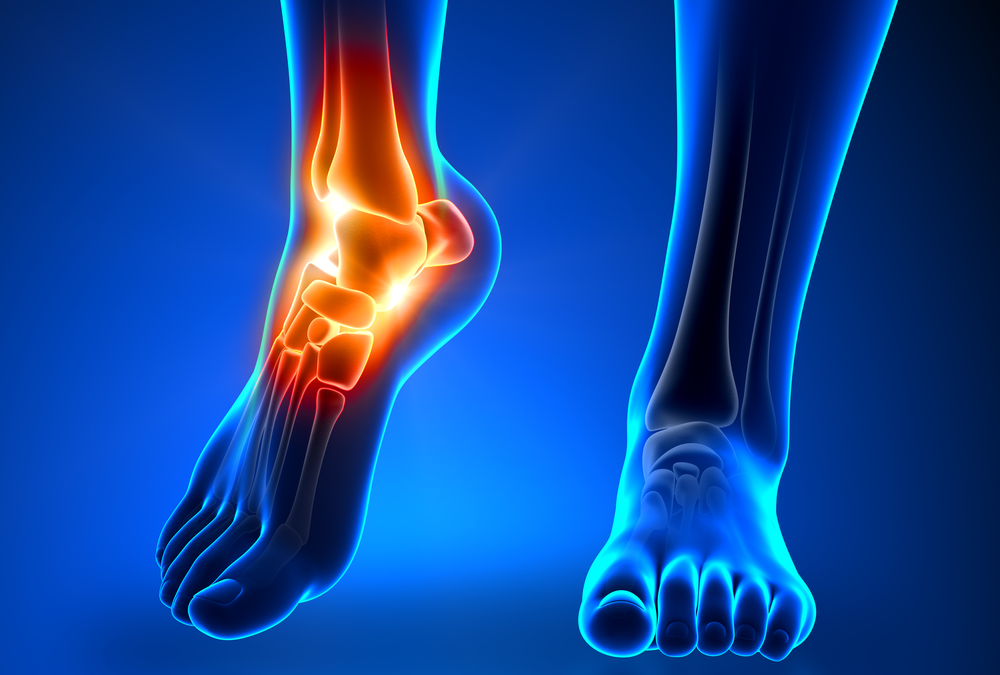

How Long Does It Take for Achilles Bursitis to Heal?

The Achilles tendon attaches the calf muscle to the heel bone. The bursa are what cushions this tendon, and when these fluid-filled sacs become inflamed, the result can be painful. If you have been diagnosed with Achilles Bursitis, the recovery period can vary. At...